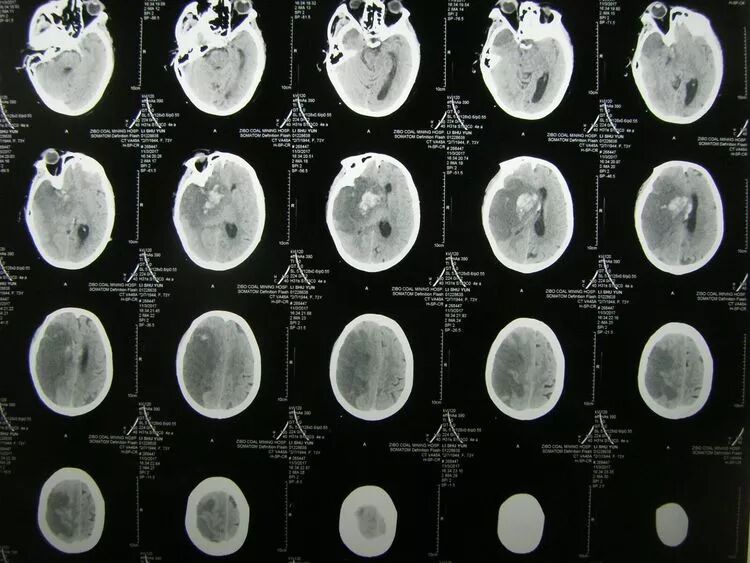

患者,女,73岁,突发言语及左侧肢体活动障碍1天伴意识不清2小时由外院转入,以往有冠心病、房颤病史多年,长期口服华法林、阿司皮林等抗凝药,查体:昏迷状,右侧瞳孔直径4mm,左侧2mm,左侧肢体瘫,经cT检查诊断为:右侧额颞顶叶大面积脑梗死并出血,右侧颞叶沟回疝,冠心病,心房纤颤。

cT显示:右侧半球大面积低密度灶,内部存在高密度出血性,中线明显移位,鞍上池及三脑室消失。